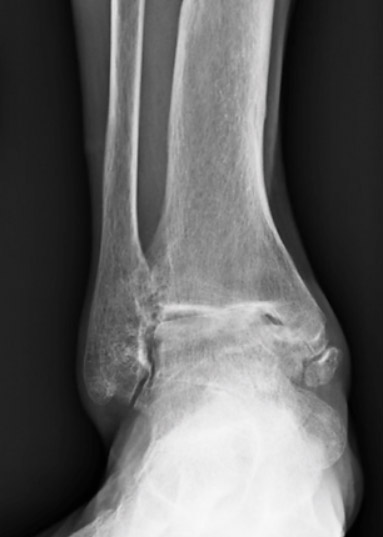

X-ray's of the same ankle before undergoing ankle fusion.

An ankle fusion involves removing any remaining cartilage in the ankle joint and causing the bone at the top of the ankle joint (the tibia) bond and become one with the bone at the bottom of the ankle joint (the talus). With an ankle fusion, the joint is "eliminated" so that the pain of arthritis is taken away. With this procedure, one also loses motion through the ankle joint. However, many patients are still able to compensate for this loss of motion with motion through the surrounding joints of the foot. Research has shown that an ankle fusion is a highly effective option for treating ankle arthritis.